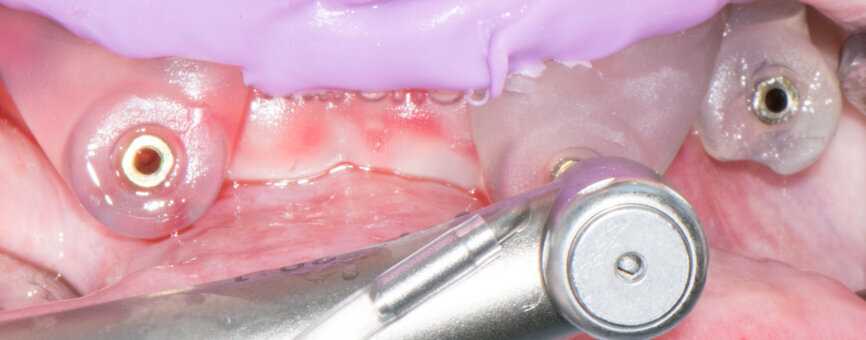

On the day of surgery, two impressions were taken: first with the guide for the pins for stable drilling (Fig. 9), then with the existing prosthesis (Fig. 10) for its correct conversion into an immediate restoration. The first mucosa-supported guide was used for drilling the sites for template fixation pins (Fig. 11). Next, the guide was removed, the flap was raised and the second guide was fixed with the pins at the corresponding sites (Fig. 12).

Implant beds were prepared (Figs. 13 & 14) and Straumann BLT implants placed with a torque setting of more than 35 Ncm, following the protocol to allow correct subsequent screw retained abutment placement (Figs. 15 & 16). Bone around the implants was prepared with bone profilers (Straumann) for the same reason (Fig. 17). The crest was flattened (Figs. 18 & 19), screw-retained abutments were screwed to 35 Ncm (Fig. 20) and covered with healing caps, and the wound was sutured (Fig. 21).